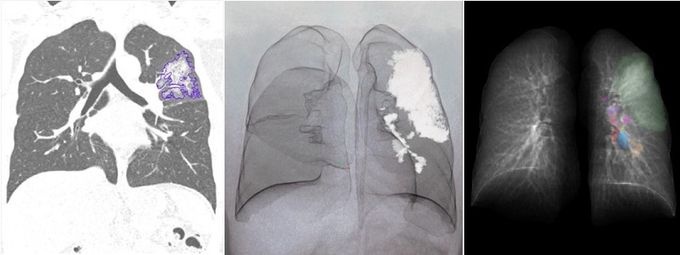

ÃÖ±Ù ±¹Á¦ ÇмúÁö¿¡ °ÔÀçµÈ ³í¹®¿¡¼­ ¼ÒÇÁÆ®¿þ¾î ‘MEDIP PRO’¸¦ ÅëÇØ Äڷγª19 ȯÀÚÀÇ ÈäºÎ CT·Î Æó·Å ÁßÁõµµ¸¦ ºÐ¼®Çϰí Á¤·®È­ÇÒ ¼ö ÀÖÀ½À» ÀÔÁõÇß´Ù.

MEDIP COVID19´Â À͸íÈ­µÈ CT ¿µ»óÀ» ºÐ¼®ÇØ 1ºÐ ³»·Î Äڷγª19 Æó·ÅÀ» ŽÁö, ºÐÇÒ, Á¤·®È­ÇÒ ¼ö ÀÖ´Â ¼ÒÇÁÆ®¿þ¾î·Î, MEDIP PROÀÇ ±â¼ú·Â¿¡ ±â¹ÝÇØ °³¹ßµÆ´Ù.

¸ÞµðÄþÆÀÌÇÇ È¨ÆäÀÌÁö¸¦ ÅëÇØ ´©±¸³ª ¹«·á·Î ´Ù¿î·Îµå ¹ÞÀ» ¼ö ÀÖ¾î ÇâÈÄ Àü ¼¼°è ÀÇ·á±â°ü¿¡ µµÀ﵃ Àü¸ÁÀÌ´Ù. ÀÌ¹Ì ¼ÒÇÁÆ®¿þ¾î °ø°³ ÈÄ 2ÁÖ¸¸¿¡ 24°³±¹, 396°³ ÀÇ·á±â°ü¿¡¼­ ´Ù¿î·Îµå ¹Þ´Â µî ¶ß°Å¿î °ü½ÉÀ» ¹Þ°í ÀÖ´Ù.